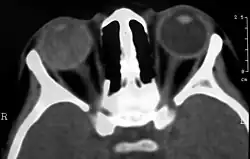

Bildgebende Verfahren wie Sonographie, Computertomographie (CT) und Magnetresonanztomographie (MRT) können zur Diagnosefindung beitragen. Sonographisch imponiert der Morbus Coats als Echogenität im hinteren Bereich des Glaskörpers ohne Schallschatten; Einblutungen in den Glaskörper und die Netzhaut sind typisch.[22][23]

Im CT stellt sich der Augapfel aufgrund des eiweißhaltigen Exsudats dichter (hyperdens) im Vergleich zum Gesunden dar. Das Exsudat kann im fortgeschrittenen Stadium den gesamten Glaskörper betreffen. Der vordere Rand des subretinalen Exsudates stellt sich durch eine Kontraststeigerung dar. Da die Netzhaut um die Papille des Sehnerven herum fixiert ist, sind fortgeschrittene Ablösungen V-förmig.[6]